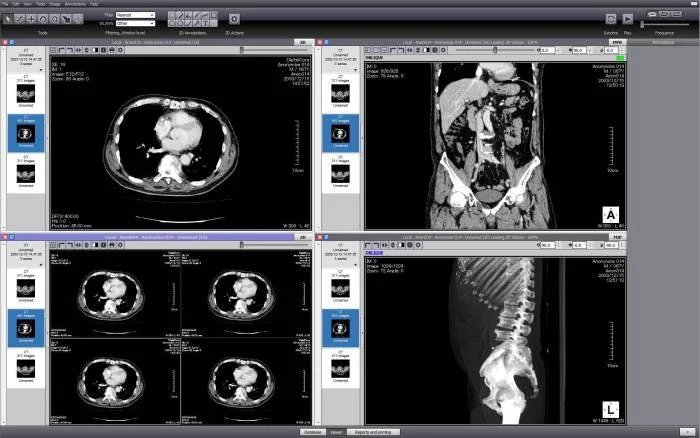

Стандарт позволяет организовать цифровую связь между различным диагностическим и терапевтическим оборудованием, использующимся в системах различных производителей. Рабочие станции, Компьютерные (КТ) и Магнитно-резонансные Томографы (МРТ), микроскопы, УЗ-сканеры, общие архивы, хост-компьютеры и мэйнфреймы от разных производителей, расположенные в одном городе или нескольких городах, могут "общаться" друг с другом на основе DICOM с использованием открытых сетей по стандартным протоколам, например TCP/IP.

Популярные программы для просмотра DICOM-файлов (Windows, macOS, iOS, Android и Linux)

Видео-обзор лучших программ для просмотра DICOM-файлов